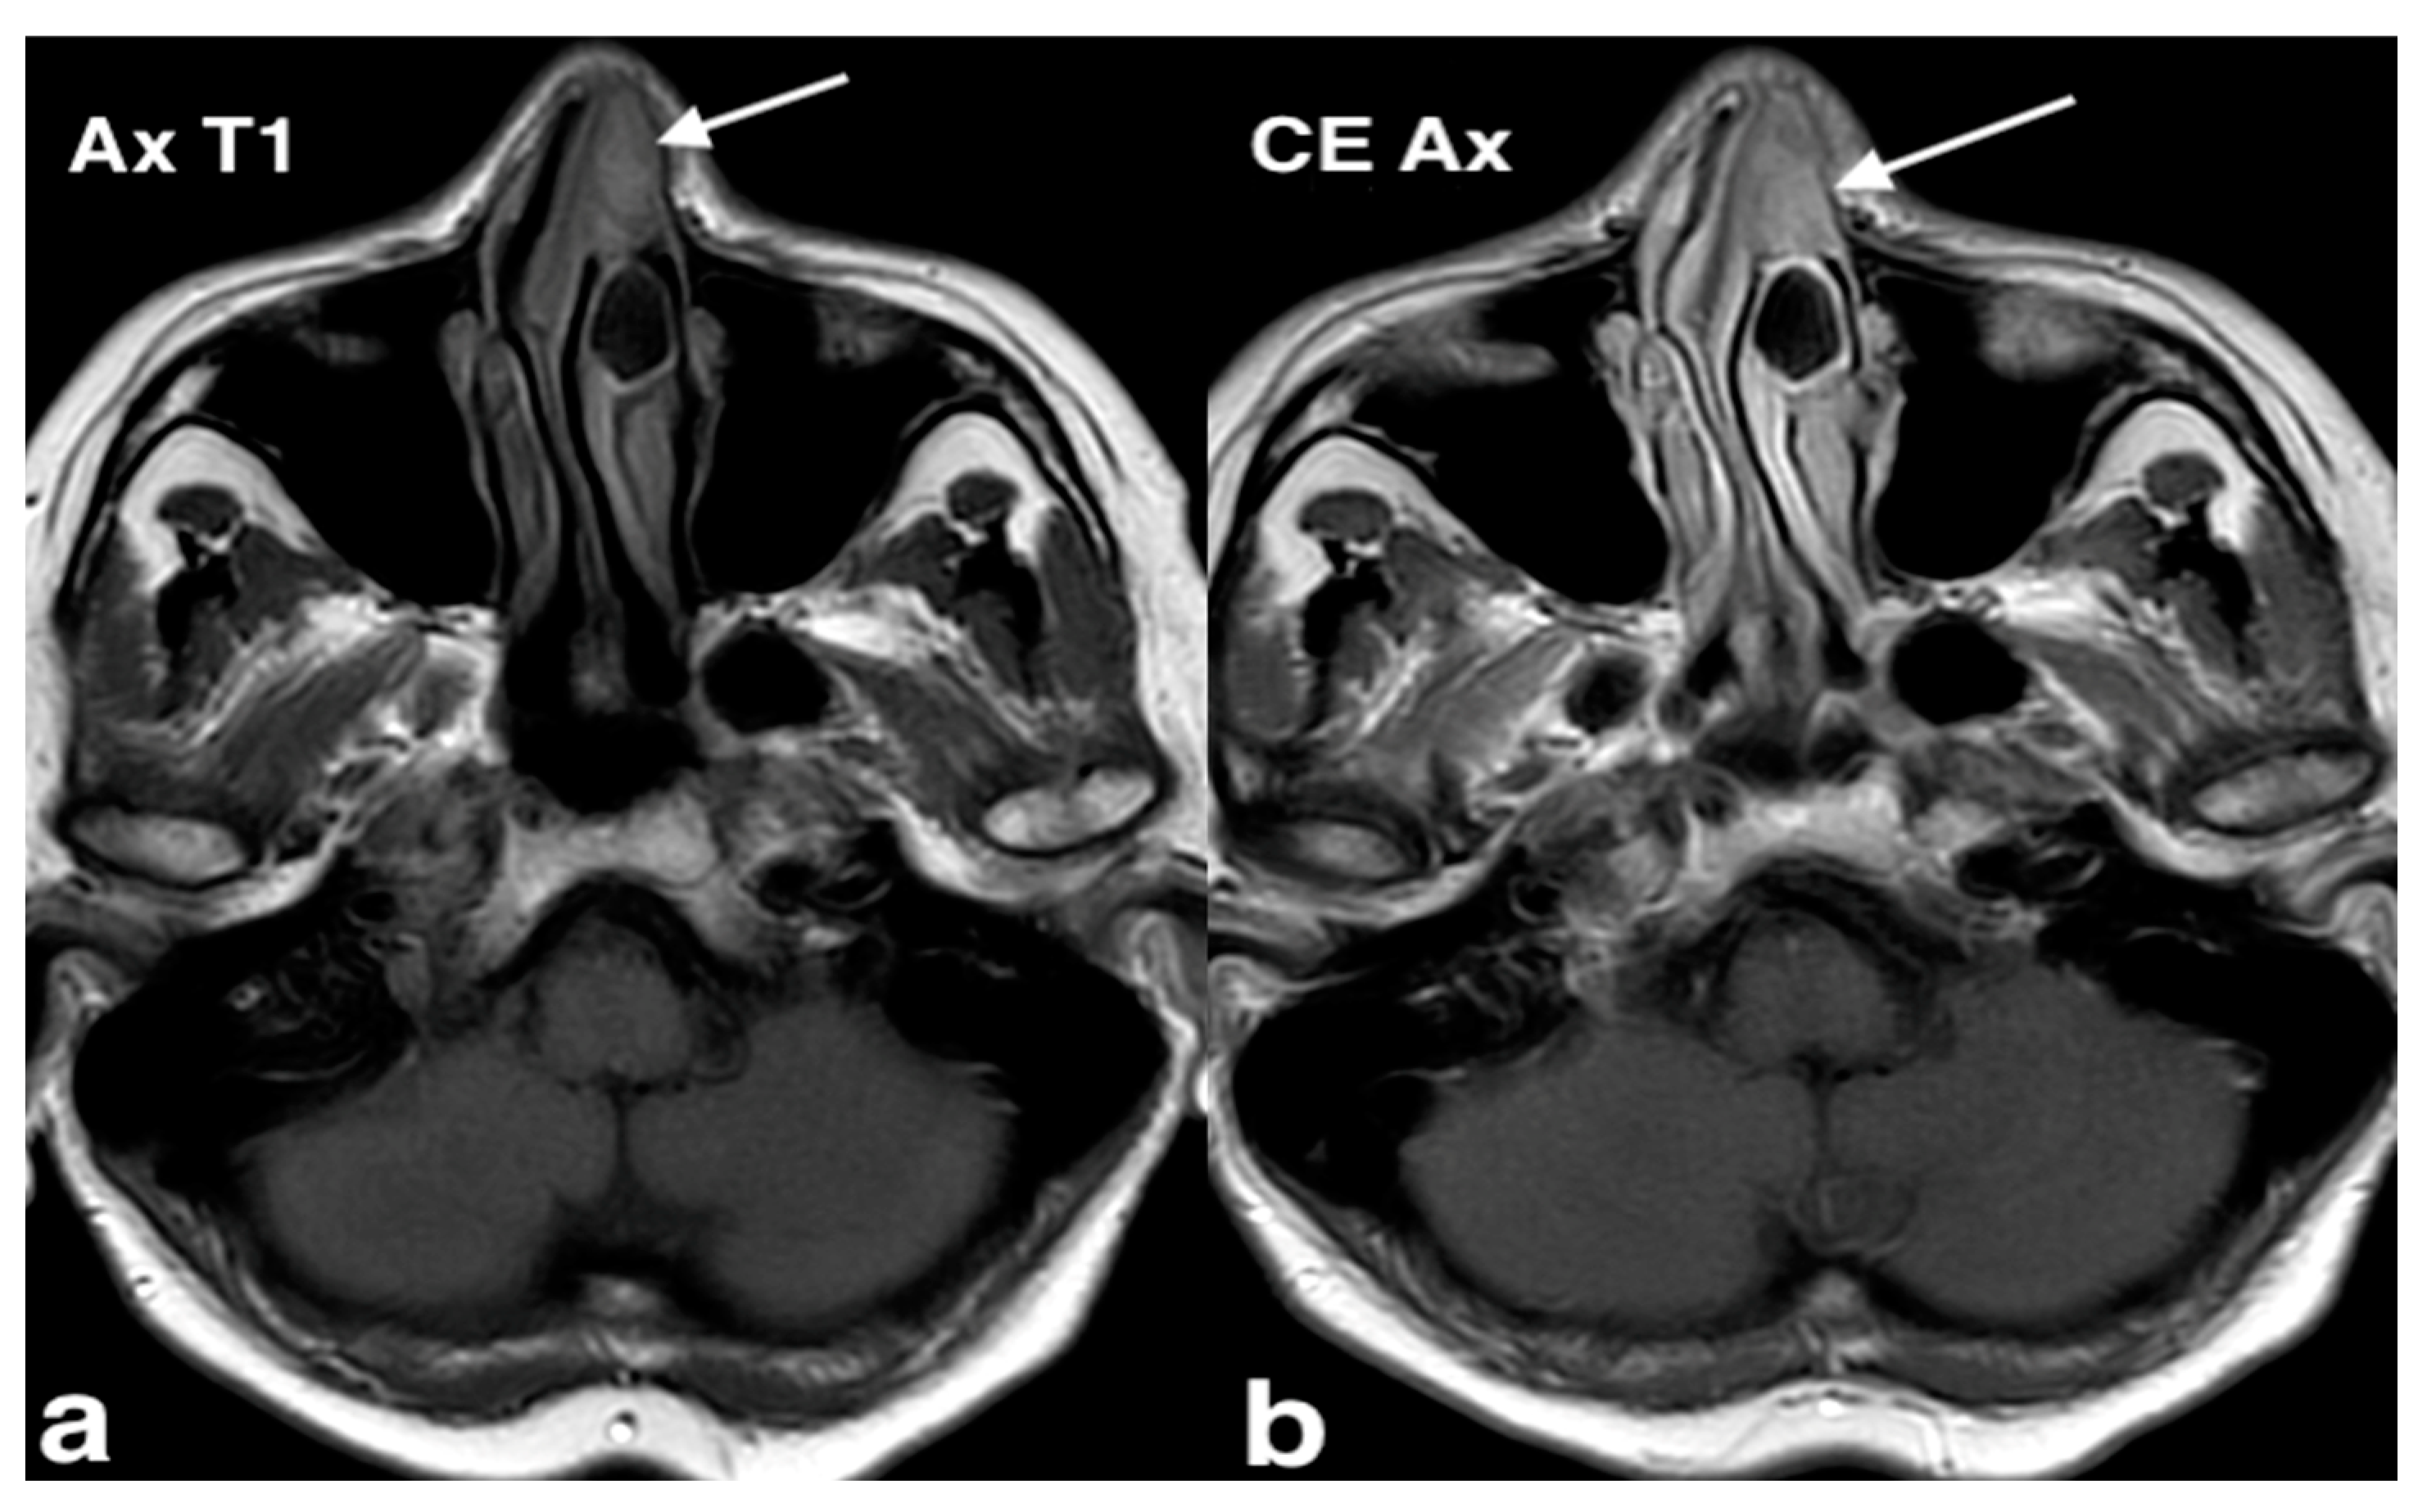

3.1.1. Septal Mucocele